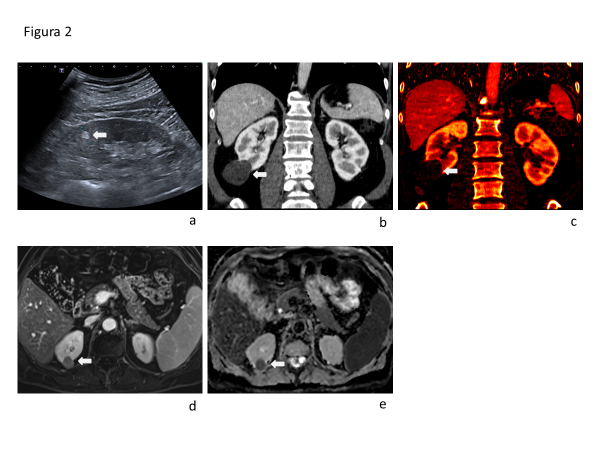

La ecografía presenta capacidad limitada para diferenciar lesiones benignas de malignas. La clásica apariencia hiperecogénica del AML no es específica, y puede presentarse en CCR pequeños (fig 2a).

La detección de grasa macroscópica en una lesión es muy sugerente de AML. En TC se manifiesta como áreas de densidad menor de -10UH. En RM la grasa macroscópica intratumoral presenta intensidad de señal similar a la grasa subcutánea e intraabdominal en todas las secuencias, característicamente con saturación de señal en secuencias de saturación grasa y con artefacto de tinta china en la interfaz agua-grasa periférica en secuencia T1 en fase opuesta. Algunos AML son pobres en grasa y no muestran grasa macroscópica en estudios de imágenes. Estos AML pobres en grasa pueden ser hipointensos en secuencia T2 al igual que los CCRp. Un patrón de impregnación hipervascular intenso favorece el diagnóstico de AML.

Por otro lado, la presencia de necrosis y áreas de hemorragia en una masa renal son sugerentes de CCR y no de lesiones benignas(17).

La diferenciación entre lesiones quísticas y sólidas tiene buen rendimiento en ecografía, TC y RM. La presencia de vascularización al doppler color o poder, o la evidencia de impregnación con contraste endovenoso son hallazgos patognomónicos de lesiones sólidas. En ocasiones es difícil hacer esta definición debido a la presencia de pseudorealce en TC o por la naturaleza hipovascular de la lesión. La TCMD de doble energía (DECT) permite, mediante separación de materiales, realizar mapas de yodo, y así mostrar de manera certera solo las estructuras que captan contraste (Fig. 2b y 2c). La RM mediante técnica de sustracción de fases también permite reconocer estructuras o lesiones que captan contraste (Fig. 2d).

La cuantificación de restricción a la movilidad de protones en secuencia de difusión (DWI) puede potencialmente ser de ayuda para diferenciar lesiones benignas de malignas. Se reportan valores de ADC significativamente menores para CCR que para lesiones benignas (Fig. 2e), siendo particularmente significativa la diferencia con los oncocitomas que presentan valores de ADC más altos. Los AML, sin embargo, pueden presentar valores de ADC bajo, incluso menores que los de CCR.